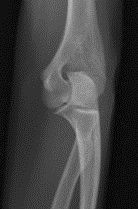

| Lateral Elbow | The elbow is elevated above the level of the shoulder radial head anterior to coronoid - should be superimposed capitulum too proximal to trochlea radial tuberosity seen - hand is pronated |

| Lateral Elbow | Elbow is depressed below the level of the shoulder radial head superimposed by coronoid capitulum too distal to medial trochlea |

| Lateral Elbow | the distal wrist is elevated hand is pronated because you can see the radial tuberosity - should not see that |

| Lateral Elbow Evaluation Criteria | ANATOMY: distal humerus, proximal forearm, entire elbow joint CRITERIA: humeral epicondyles are superimposed radial tuberosity is invisible (if visible the hand is pronated) half of the radial head superimposed by coronoid process Elbow is flexed 90 degrees to see/not see fad pads 3 concentric arcs visible POSITIONING: CR perpendicular @ lateral epicondyle |